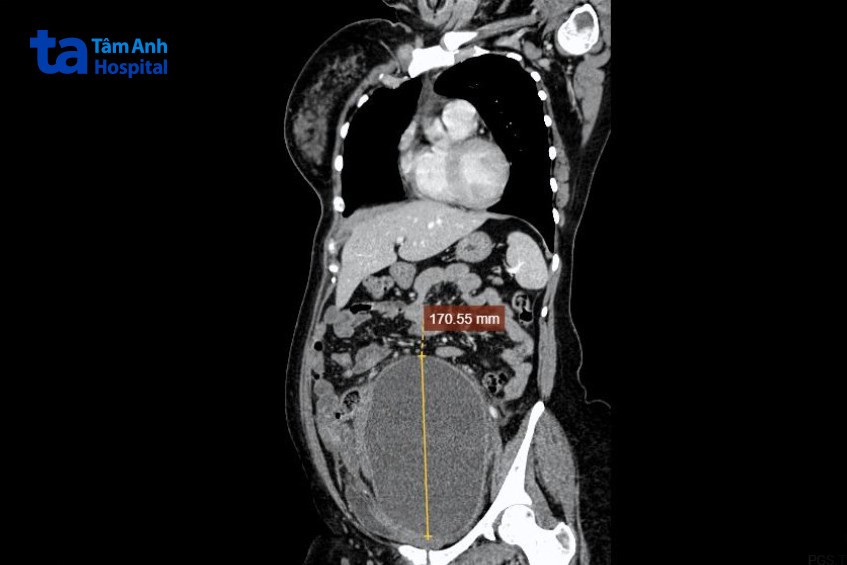

TTƯT.PGS.TS Triệu Triều Dương, Giám đốc chuyên môn Ngoại khoa, BVĐK Tâm Anh Hà Nội cho biết, dựa trên chẩn đoán hình ảnh và các xét nghiệm thăm khám xác định người bệnh có ổ áp xe nhiễm trùng (khối viêm mạn tính), trọng lượng khoảng 6 kg, tương đương với thai 9 tháng. Khối tổn thương phát triển với kích thước lớn chiếm toàn bộ thể tích ổ bụng, kéo dài từ thượng vị đến tiểu khung, chèn ép các tạng xung quanh, gây giãn thận niệu quản hai bên, có triệu chứng của tắc ruột do u hoại tử vào thành sigma trực tràng, gây tổn thương hệ mạch vùng chậu. Mô nội mạc tử cung của người bệnh xuất hiện ở khắp phần tiểu khung như cơ bàng quang, tử cung, đại tràng…